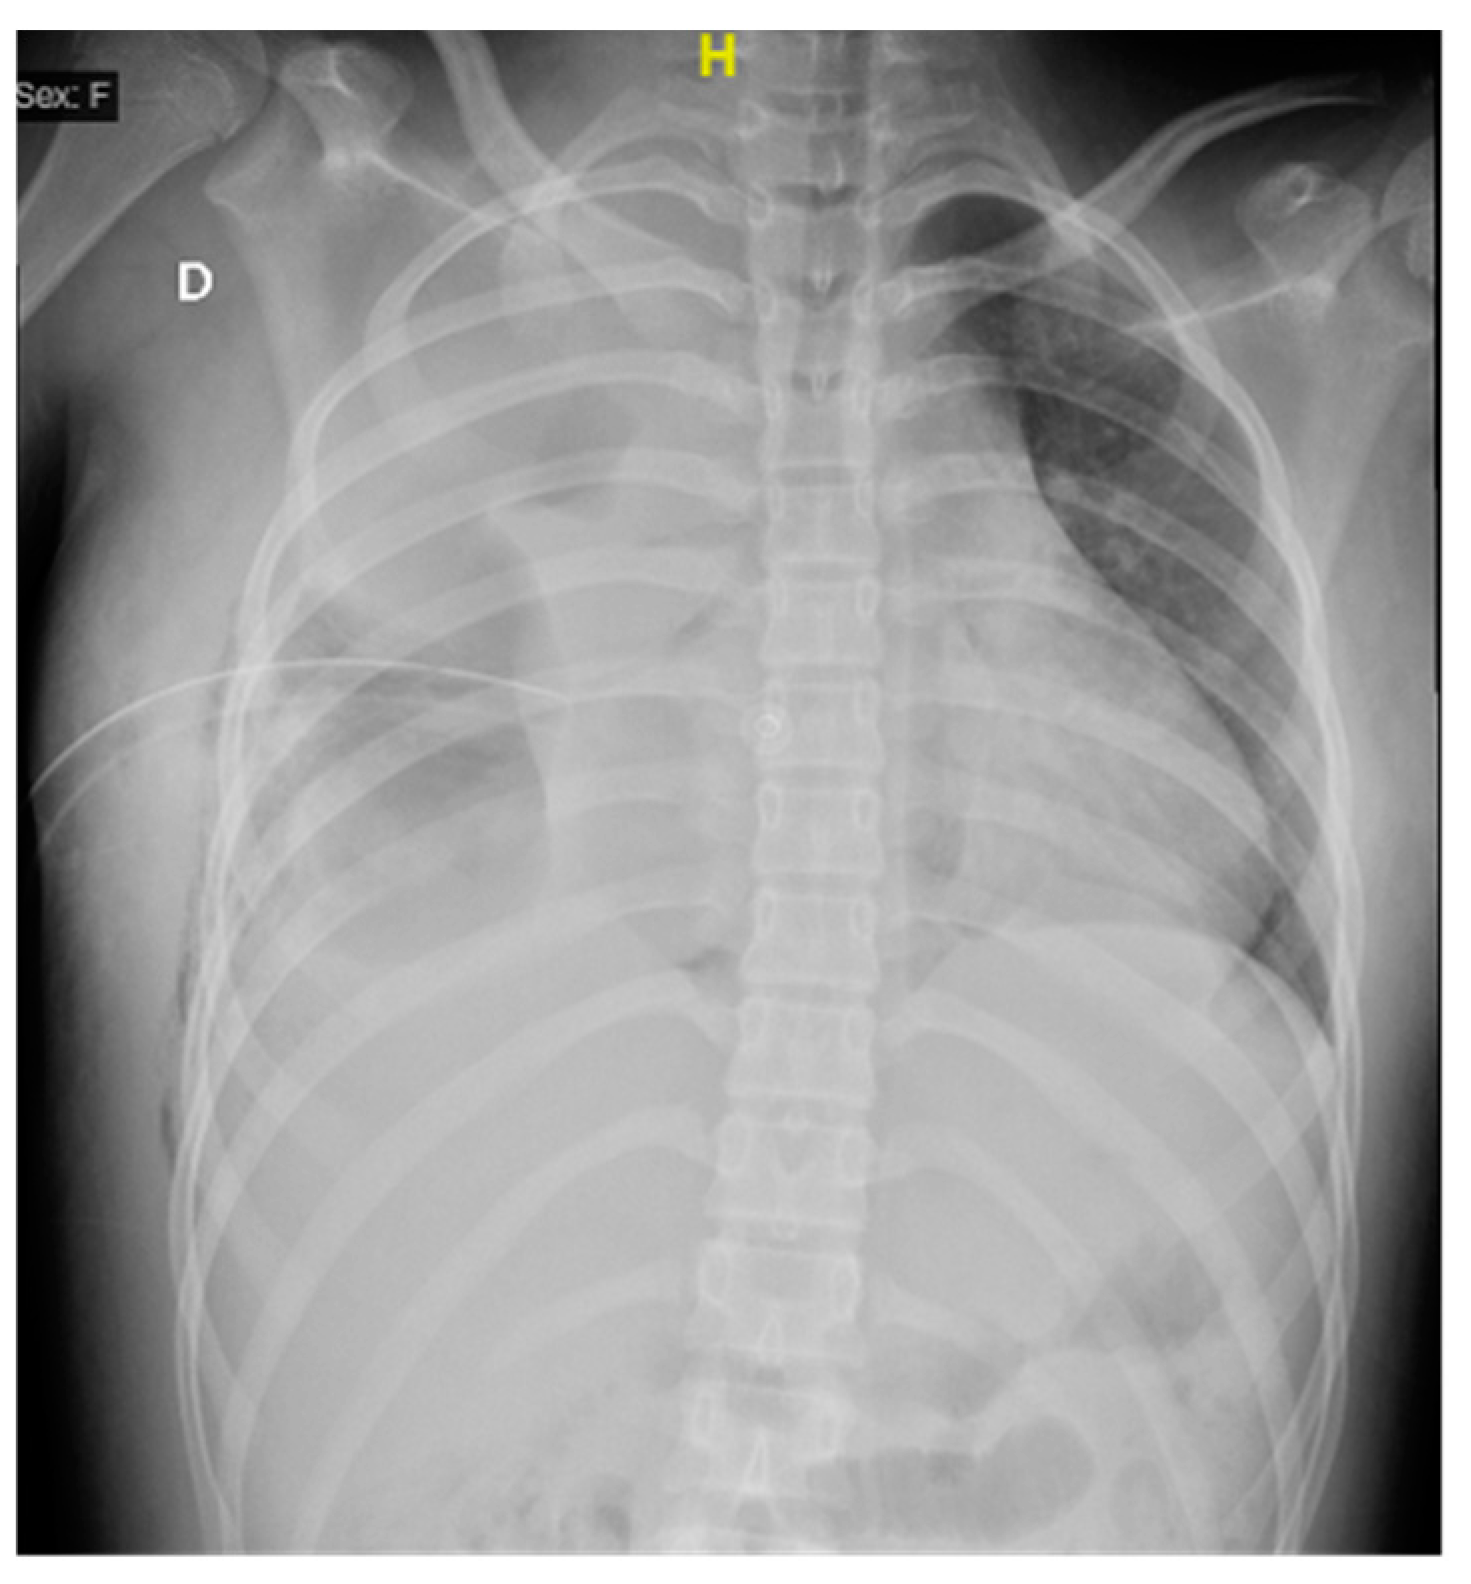

2. Case Presentation